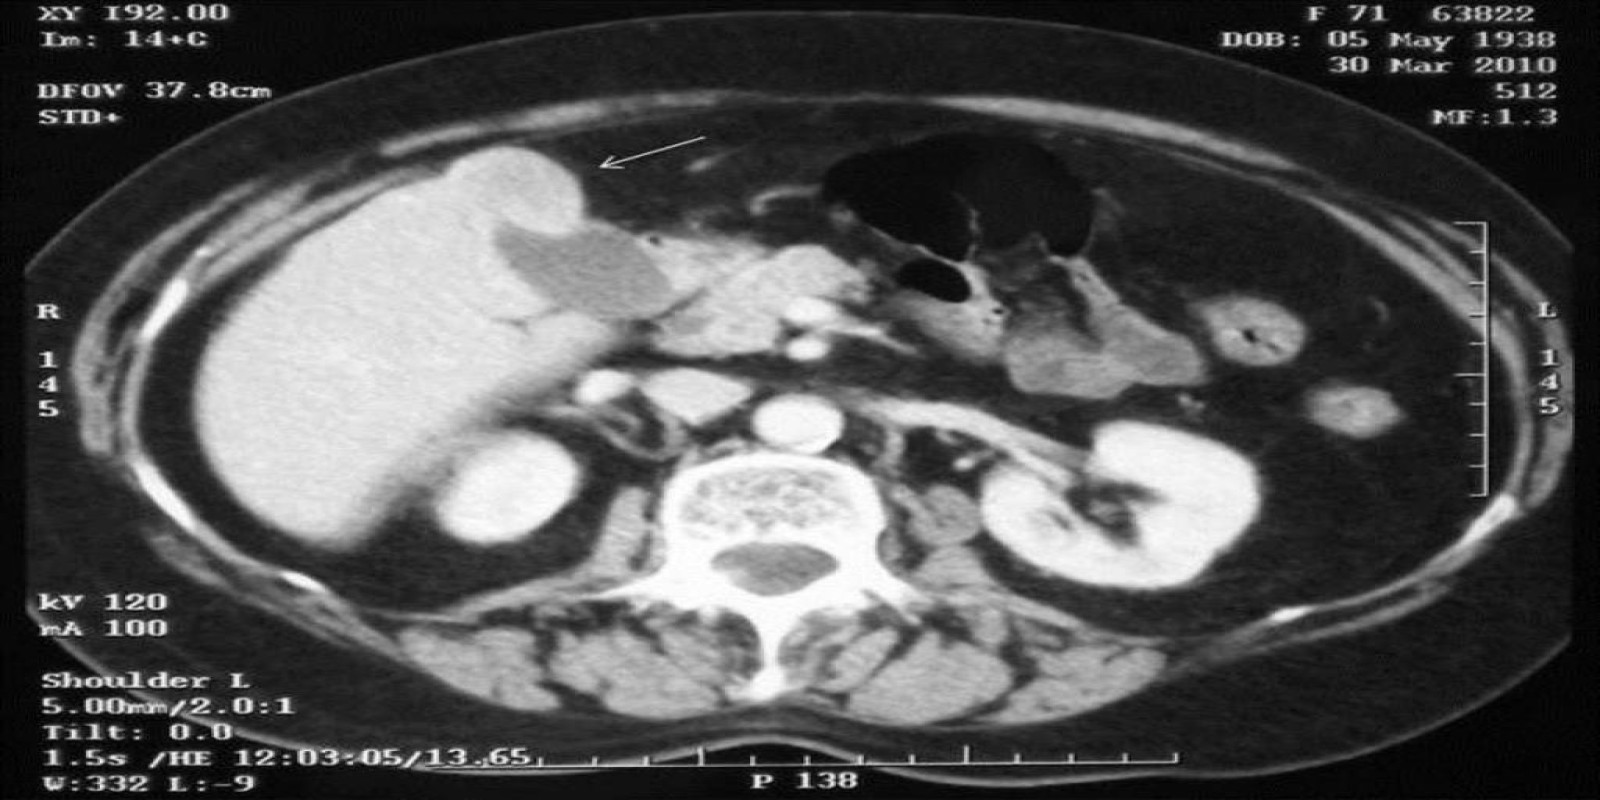

Caso Código 025B de Câncer da Vesícula Biliar

Cod.: 025B